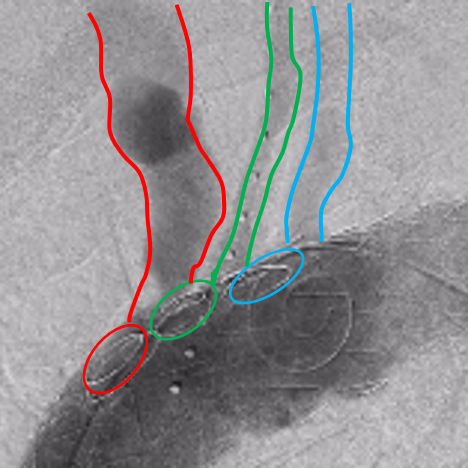

独特的自适应特性

具备强大自适应能力,即使主体支架窗口与分支血管存在较远错位,仍可通过支架结构容错性完成精准植入。经科技部查新确认,该技术方案国内外均无类似报道,具有显著创新性。

主体支架释放后造影

主体支架窗口

与分支动脉开口存在偏差

利用自适应性成功超选左颈总动脉,并置入分支支架

利用自适应性成功超选无名动脉,并置入分支支架

利用自适应性成功超选左锁骨下动脉,

并置入分支支架

术后造影